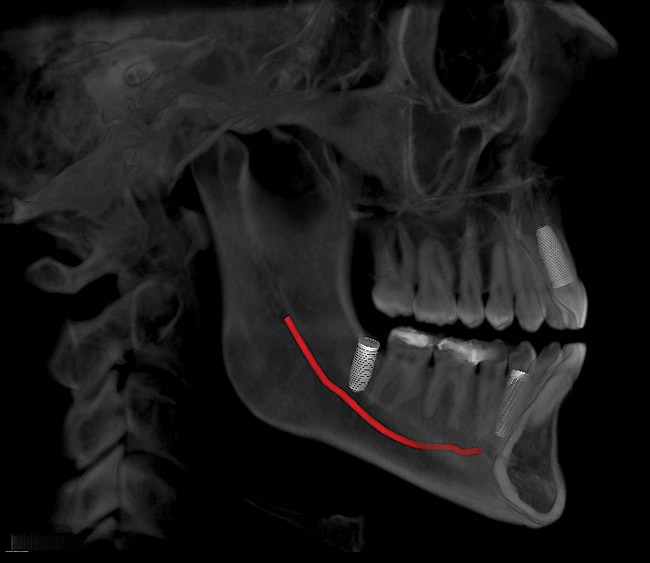

A conventional computed tomography (CT) apparatus, which is generally designed for body imaging, tends to be large in size and delivers a high radiation dose to the patient; it is also very expensive (Figure 1).2 An excellent tool for dental implant placement (Figure 2), cone beam is ideal for maxillofacial imaging.2 Its superior imaging provides details of bone morphology and bone dimensions, as well as locations of vital structures, by producing cross-sectional images along the arch (Figure 3).5,12 The apparatus is used for pre-implant evaluation, treatment planning, and the actual placement process. In addition, it is useful in follow-up evaluation of the implant (Figure 4). In terms of CBCT’s value in the pre-implant process, the ability of this imaging process to evaluate the quality of the bone in the designated implant location is outstanding. The 3D technology available with cone-beam computed tomography enables the volume (thickness and composition) of the bone to be easily evaluated in different areas. This is helpful in terms of guiding the practitioner during the implant process.3,14

Figure 3  Implant placement planning.

Figure 3

Figure 4  A postoperative evaluation.

Figure 4